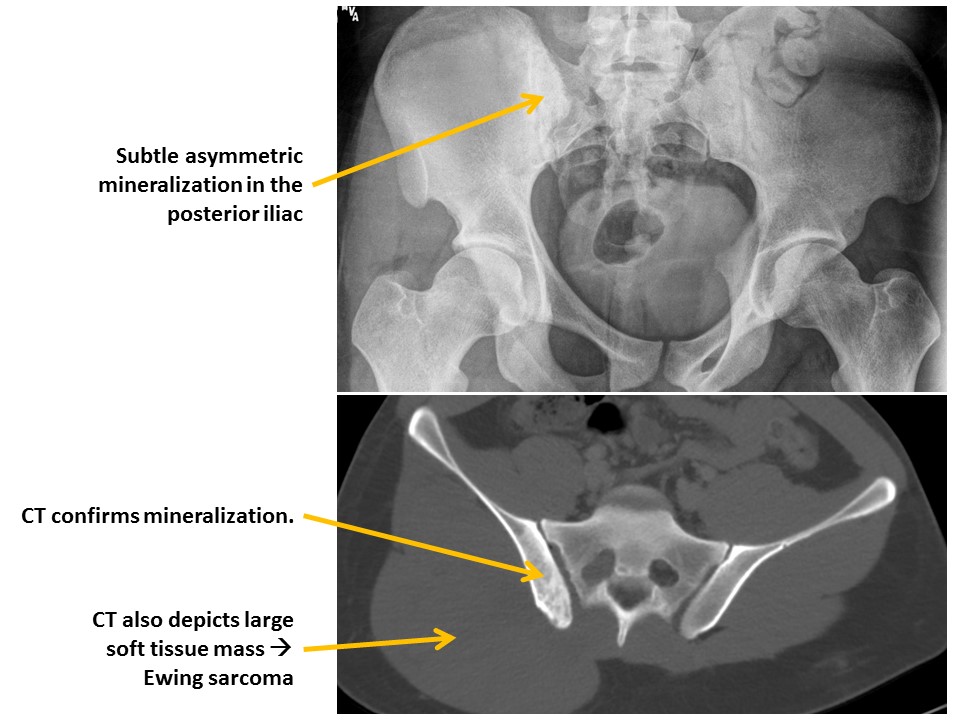

ILIAC BONES

Iliac wing fractures are present. [Yes/No]

Posterior iliac bone fractures are present. [Yes/No]

MISCELLANEOUS

The osseous mineralization is diffusely abnormal. [Yes/No]